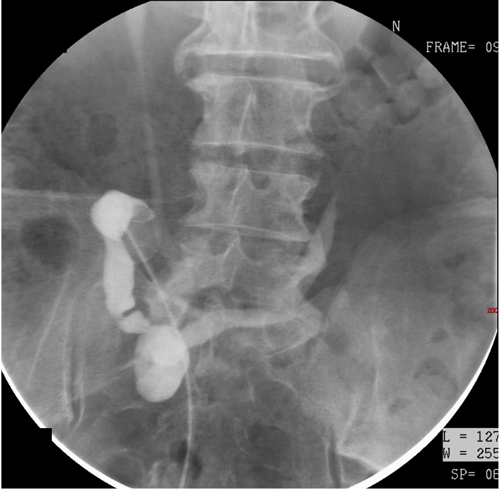

Case 3

- A cystogram has been performed. Although the image looks like an intravenous urogram (IVU), the bladder is too densely opacified with contrast for this to be part of an IVU series. The bladder has been distended with contrast during the cystogram.

- Dense opacification of the urinary bladder is seen, which has a smooth outline and appears normal. Contrast is seen to reflux into both ureters and collecting systems which should not be seen as part of a routine cystogram.

- The patient has marked reflux (grade 4). Reflux is graded from 1 to 5, as below:

- Grade 1 - reflux limited to the ureter

- Grade 2 - reflux up to the renal pelvis

- Grade 3 - mild dilatation of the ureter and pelvicalyceal system

- Grade 4 - tortuous ureter with moderate dilatation

- Grade 5 - tortuous ureter with severe dilatation of ureter and pelvicalyceal system. Loss of fornices and papillary impressions.

Sometimes, reflux is not seen during a routine cystogram, but if there is clinical suspicion, further images should be obtained during micturition to assess for mild reflux.